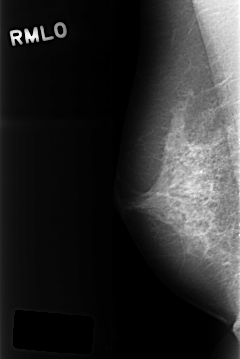

C_0320_1.RIGHT_MLO

RIGHT_MLO LINES 4304 PIXELS_PER_LINE 2872 BITS_PER_PIXEL 12 RESOLUTION 50 NON_OVERLAY